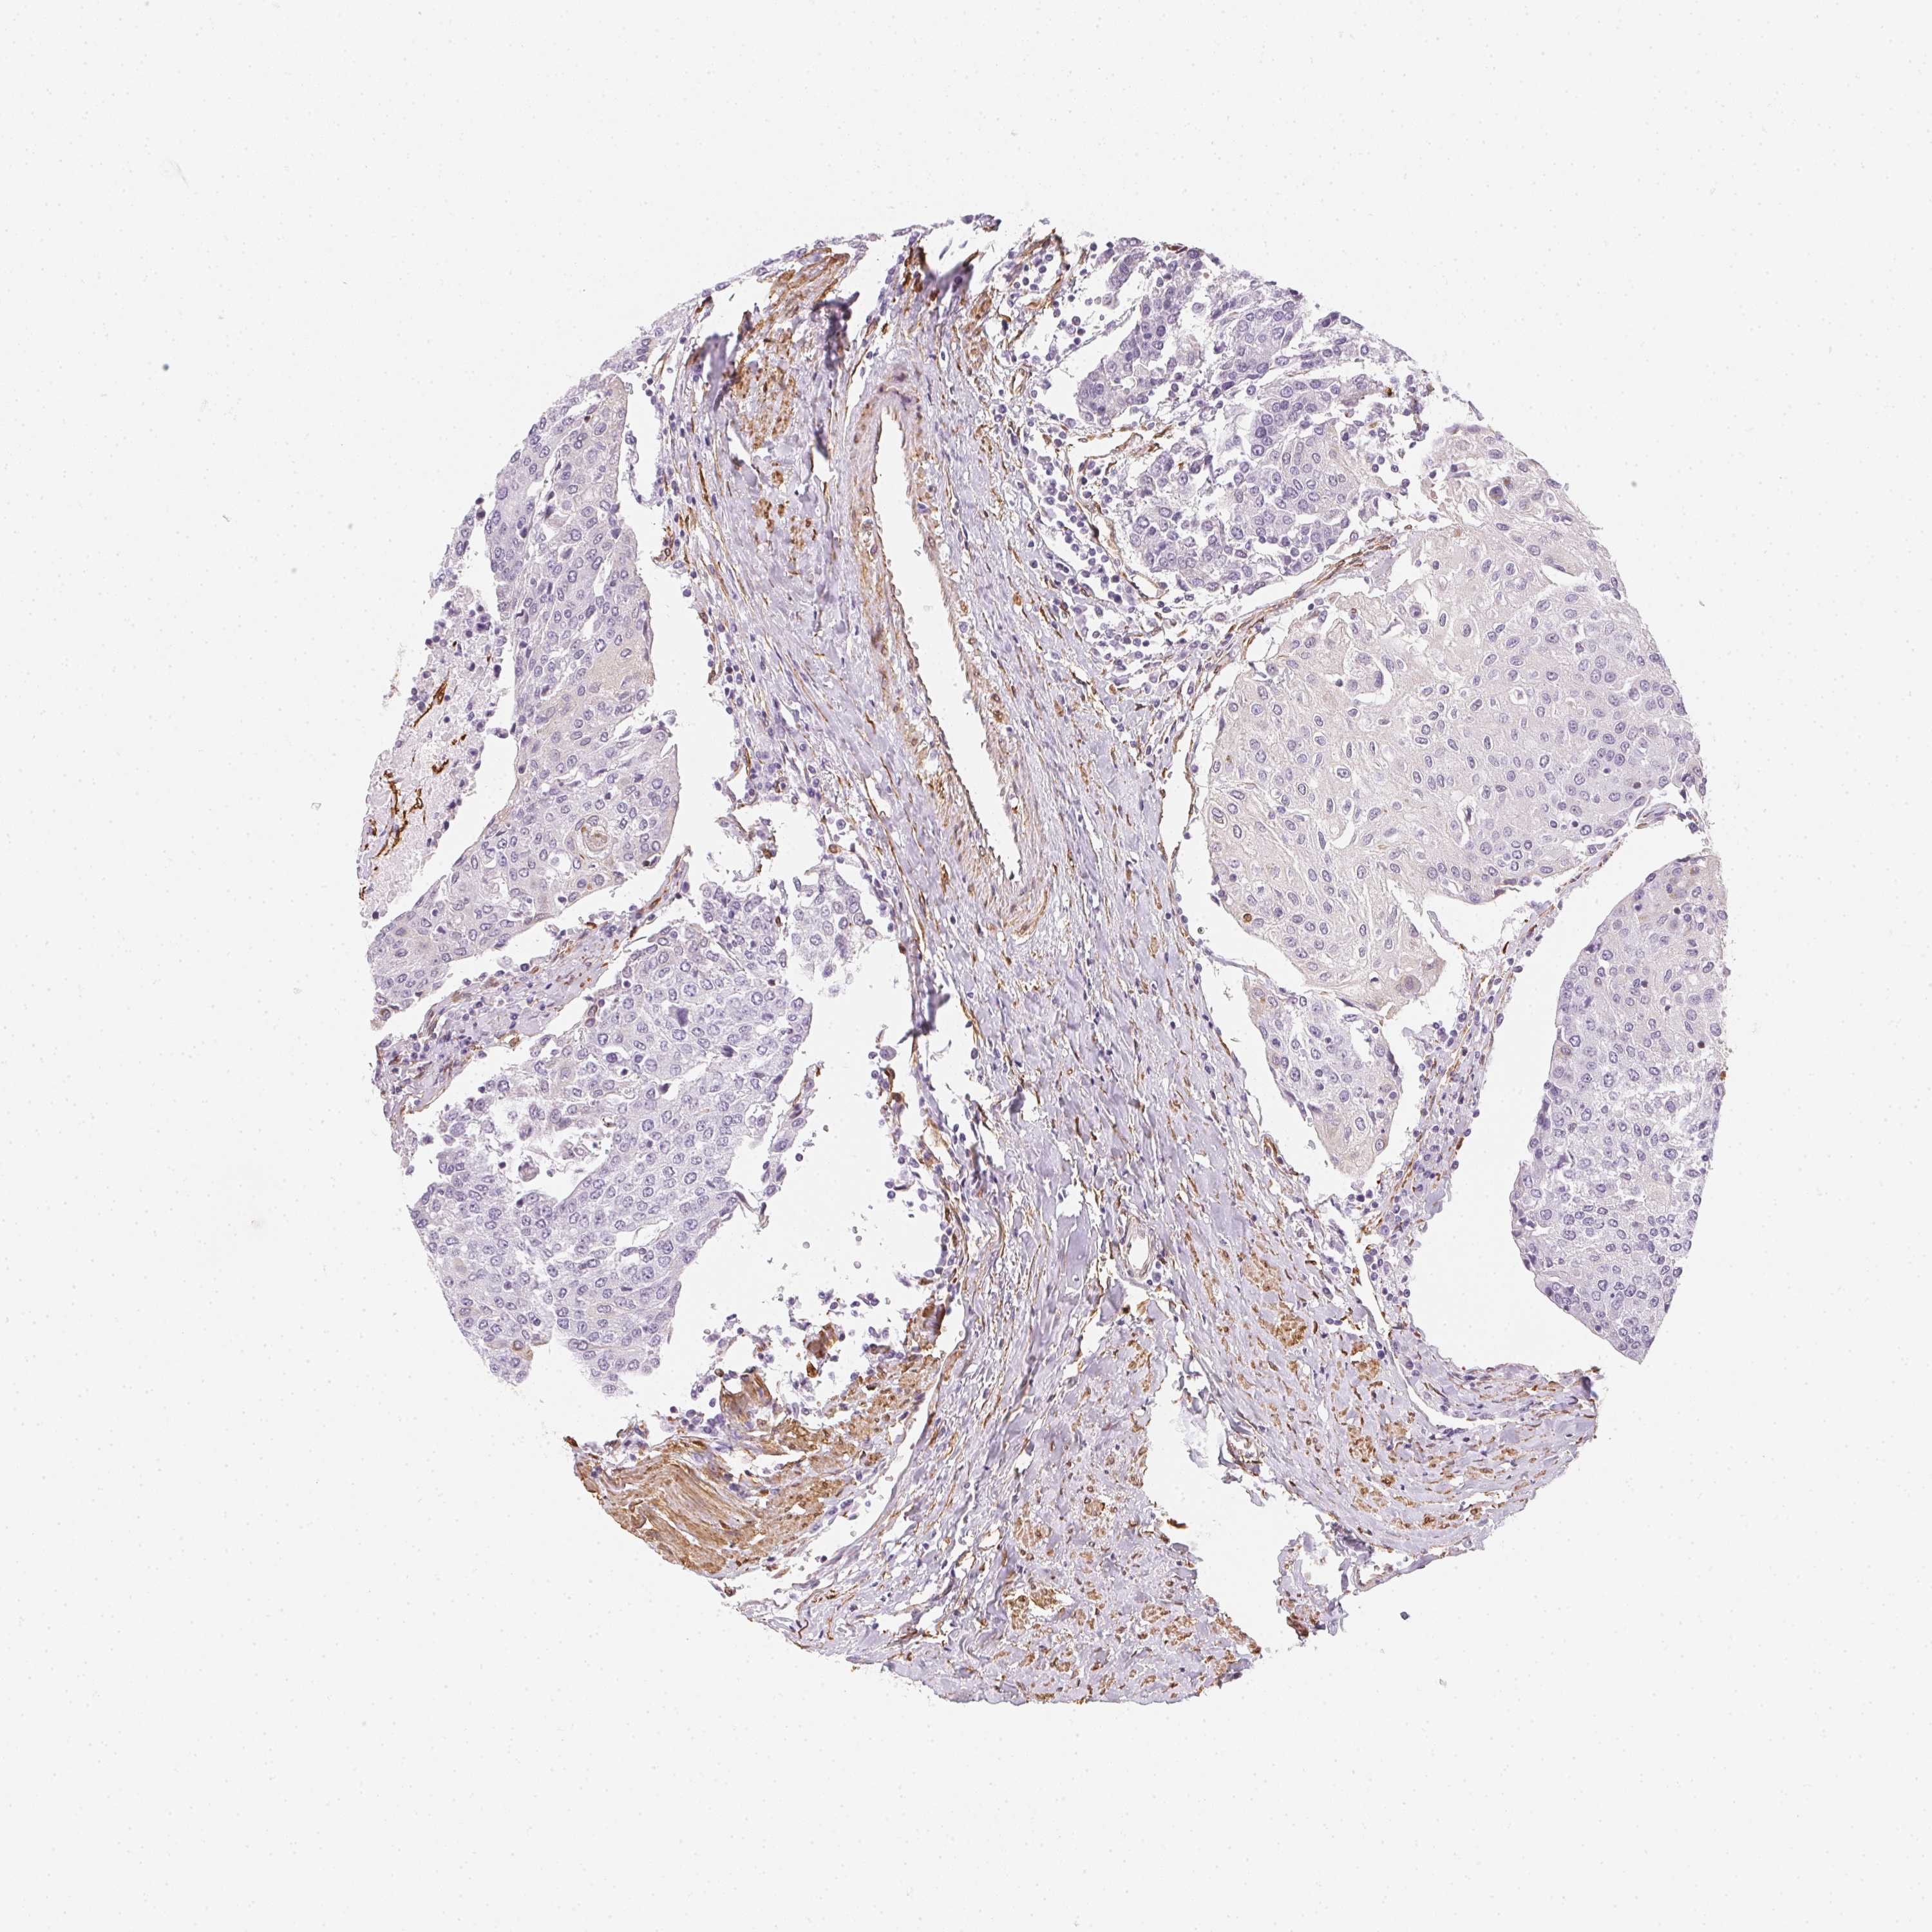

UROTHELIAL CANCER - Protein expressioni

A mouse-over function shows sample information and annotation data. Click on an image to view it in a full screen mode. Samples can be filtered based on level of antibody staining by selecting one or several of the following categories: high, medium, low and not detected. The assay and annotation is described here.

Antibody stainingi

Antibody staining in the annotated cell types in the current human tissue is reported as not detected, low, medium, or high, based on conventional immunohistochemistry profiling in selected tissues. This score is based on the combination of the staining intensity and fraction of stained cells.

Each image is clickable and will lead to virtual microscopy that enables deeper exploration of all samples and also displays staining intensity scores, fraction scores and subcellular localization as well as patient and tissue information for each sample.

Antibody HPA042124

Antibody HPA049484

Staining

High

Medium

Low

Not detected

Intensity

Strong

Moderate

Weak

Negative

Quantity

>75%

75%-25%

<25%

None

Location

Nuclear

Cytoplasmic/membranous

Cytoplasmic/membranous,nuclear

Urothelial carcinoma, High grade

Urothelial carcinoma, Low grade